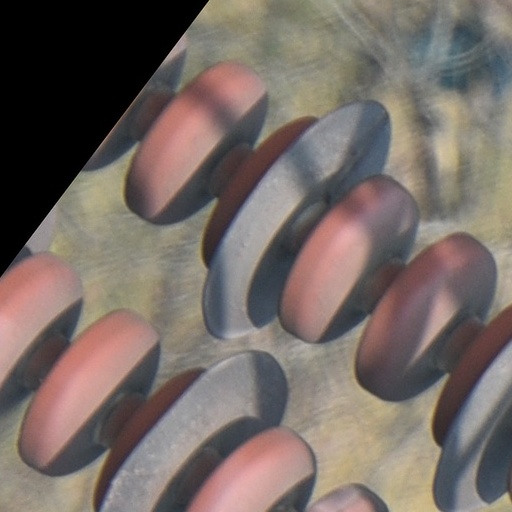

512x512px

512x512px